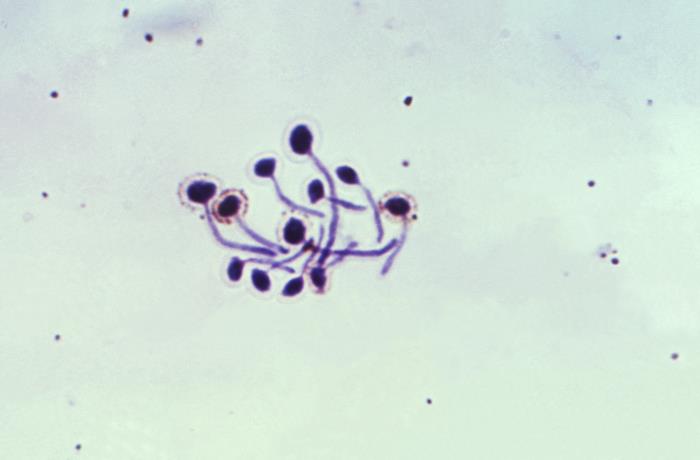

顯微鏡下的白假絲酵母菌

白假絲酵母菌屬于念珠菌屬又稱為白色念珠菌。念珠菌屬有270余種,其中的10個種有致病性。白假絲酵母菌是本屬最常見的致病菌,可引起皮膚、口腔、黏膜和內(nèi)臟的急、慢性感染,即假絲酵母菌病。那么如何檢測白假絲酵母菌?可以采用培養(yǎng)基和顯微鏡檢查法。

在生物顯微鏡下,菌體呈無色透明,但具有高折光反射,使其易于識別。圓形或卵圓形,直徑3-6μm,革蘭染色陽性,著色不均,以芽生方式繁殖。